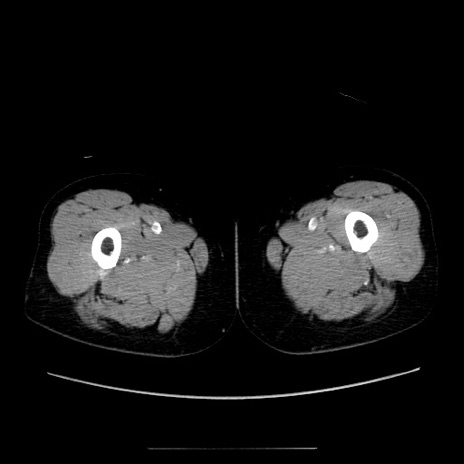

冠状断像

【症例】70歳代女性

【主訴】お腹が張る

【現病歴】1週間くらい前から腹部膨満の自覚あり。昨日夜から増悪したため、本日救急外来受診。

【身体所見】意識清明、BT 36.5℃、BP 165/106mmHg、HR 80bpm、SpO2 98%、腹部:膨満、軟、自発痛・圧痛なし、触診にて不快感あり、腸蠕動音:減弱

【データ】WBC 12600、CRP 1.04